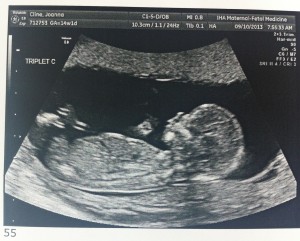

Baby C – is a BOY!

A is 170 grams, B is 175 grams and C is 178 grams so they’re all measuring well. Grow, grow, grow!